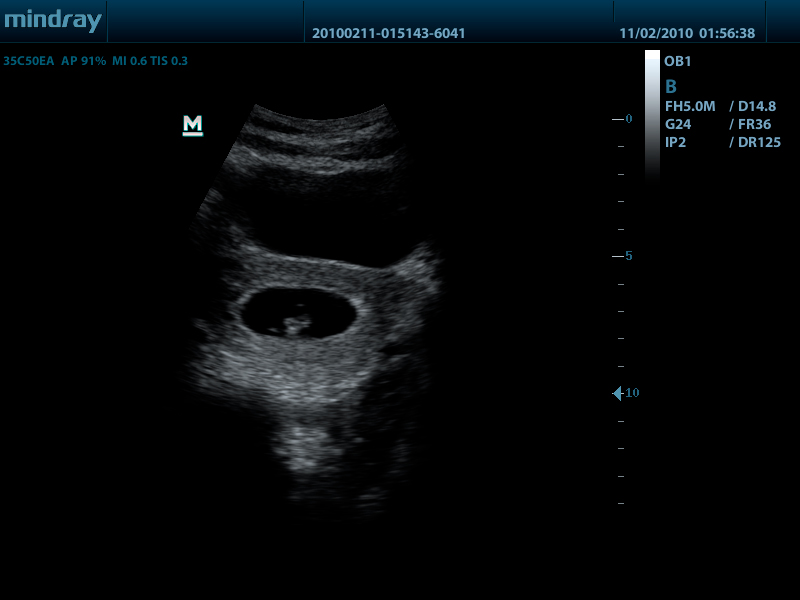

- Широкий выбор мультичастотных датчиков от 2,0 до 14,0 МГц

- Конвексный датчик 35C50EA, 1.7 - 6.0 МГц, радиус кривизны 50 мм